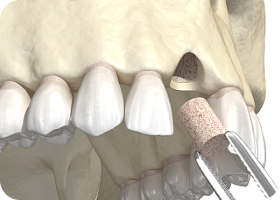

Q. 뼈이식 임플란트는 어떻게 치료하나요?

잇몸뼈는 임플란트를 지지하는 중요한 기반입니다. 하지만 시간이 지나거나 잇몸병으로 뼈가 약해진 경우엔

임플란트를 바로 심기 어렵습니다. 이럴 땐 부족한 뼈를 이식해 튼튼한 기반을 만든 뒤, 임플란트를 심는 정밀 치료입니다.

잇몸뼈가 부족한 부위에 이식재를 넣어

뼈를 보강하고, 기존 뼈와 융합될 수 있도록

안정화를 유도합니다.